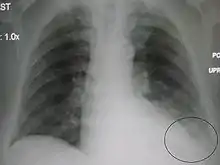

إصابة بانصباب نظير ذات الرئة بسبب إصابة بذات الرئة في الفص الأيسر السفلي.